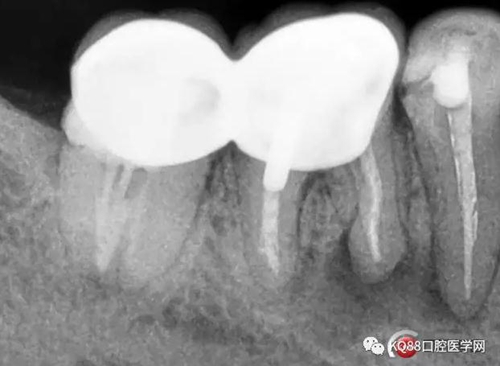

根充后X線片

46/47金瓷烤瓷聯(lián)冠修復后